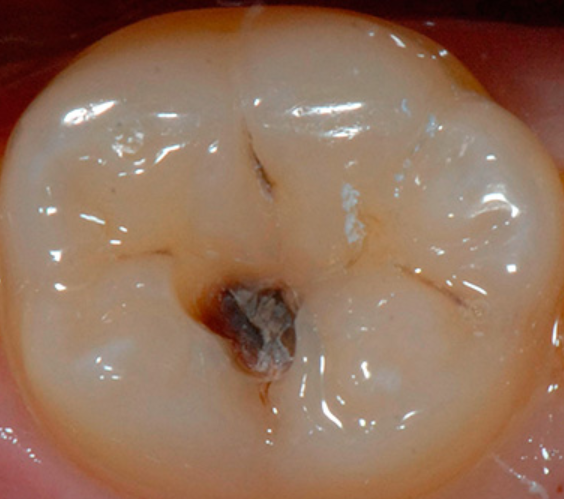

- 충치 진행 2단계

증상: 법랑질 아래 상아질이 썩는 단계,

육안으로 쉽게 파악할 수 있음

통증: 차갑거나 뜨거운 것에 반응

음식물 씹을 때 통증 있음

치료비:보통 10만 원대에서 30만 원 이하

(비급여 진료비는 치과마다 차이 있음)